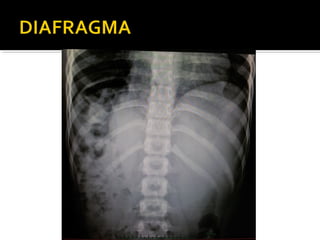

Este documento fornece parâmetros técnicos para realizar uma radiografia de tórax, incluindo posicionamento correto do paciente, dose adequada de radiação e estruturas anatômicas a serem avaliadas, como coração, pulmões, pleura, diafragma e ossos do tórax.